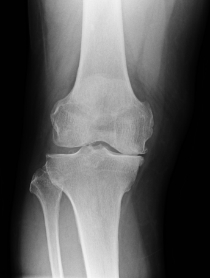

変形性膝関節症

ひざの軟骨がすり減ったり、なくなったりすることでひざの関節が変形する疾患で、痛みが生じることがあります。

加齢や肥満などはっきりとした原因がない場合は一次性、ひざの軟骨がすり減る原因が怪我や病気等はっきりしている場合は二次性と言います。

左が正常なひざ関節、右に行くほど変形が大きくなっています。

変形性膝関節症の術前

高位脛骨骨切り術

骨切り術の術後

人工膝関節全置換術(左:手術前、右:手術後)

人工関節置換術には、ひざの関節すべてを人工関節に取り換える全置換術と、変形した部分のみを取り換える単顆片側置換術があります。全置換術はデザインや材質、手術方法が確立されており、変形性膝関節症に対して最も多く行われている手術です。